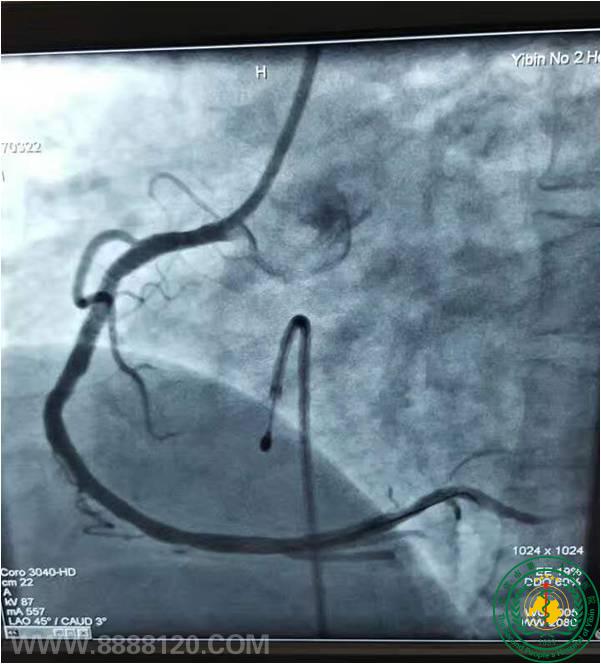

宜宾市第二人民医院 图文